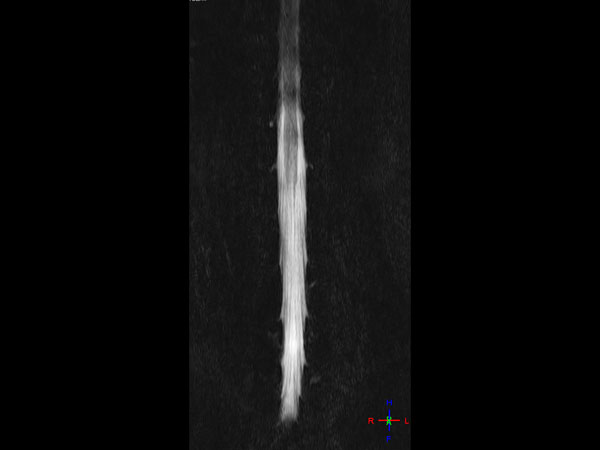

Lumbar Spine - Obese patient

32- year old male patient, 180 kg, with back pain. Was first examined on CT but quality was not sufficient for diagnosis. MRI gave excellent images. Diagnosis: small protrusion of the disc L5/S1, no meningioma.